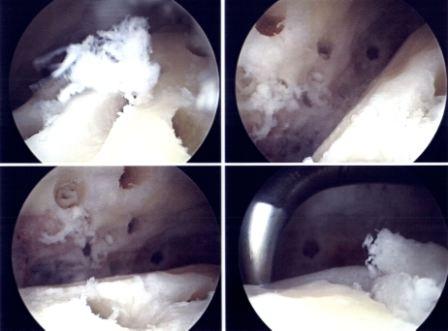

Die Gelenkstoilette kommt im Frühstadium der Arthrose zur Anwendung. Es geht dabei darum, die zum Impingement führenden Knochenwucherungen zu beseitigen und die vernarbte Schleimhaut im Bereich des vorderen oberen Sprunggelenkspaltes zu entfernen. Neben der Schmerzreduktion kann so meist auch eine Verbesserung der Gelenksbeweglichkeit erreicht werden.